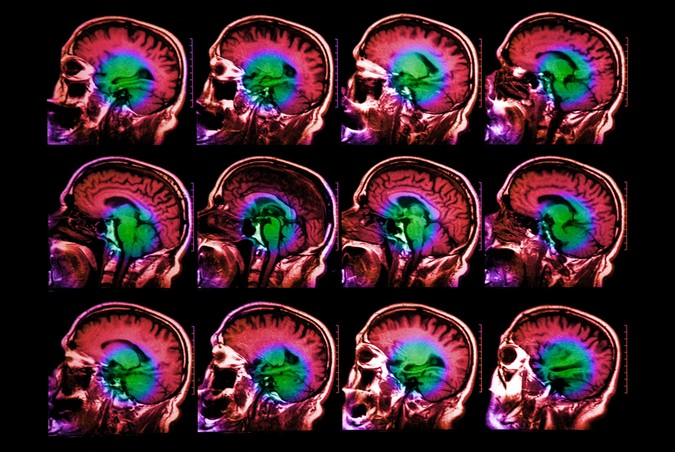

Fonksiyonel manyetik rezonans görüntüleme (fMRI) kullanarak, sinir bilimciler beynin dili işlemekten sorumlu birkaç bölgesini tanımladılar. Ancak, bu bölgelerdeki nöronların belirli işlevlerini keşfetmek zor oldu çünkü kan akışındaki değişiklikleri ölçen fMRI, küçük nöron popülasyonlarının ne yaptığını ortaya çıkaracak kadar yüksek çözünürlüğe sahip değil.

Bilim insanlarının beynin farklı bölümlerinin rolleri hakkında çok şey öğrenmelerine yardımcı olan Fonksiyonel MRI, beyindeki kan akışındaki değişiklikleri ölçerek çalışır. Bu ölçümler, belirli bir görev sırasındaki sinirsel aktivitenin bir temsilcisi olarak işlev görür. Ancak, bir fMRI görüntüsünün her “voksel”i veya üç boyutlu parçası, yüz binlerce ila milyonlarca nöronu temsil eder ve yaklaşık iki saniye boyunca aktiviteyi toplar, bu nedenle bu nöronların ne yaptığına dair ayrıntılı bilgi ortaya koyamaz.